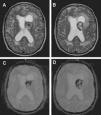

A pesar de que los cavernomas son malformaciones vasculares relativamente frecuentes en el sistema nervioso central, su localización intraventricular, especialmente en la región del foramen de Monro, es muy poco común. Esta localización atípica les confiere una serie de rasgos diferenciales, tanto clínicos como radiológicos, que pueden dificultar en extremo su diagnóstico preoperatorio y conducir a procedimientos ineficaces, como la radioterapia o el abordaje quirúrgico neuroendoscópico, e incluso peligrosos para el paciente, como la biopsia estereotáxica.

Dado lo infrecuente de la patología y con el fin de ilustrar estas dificultades diagnósticas, se presenta a continuación un caso de cavernoma intraventricular de la región del foramen de Monro.